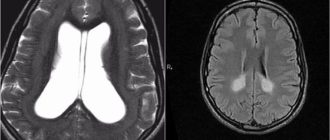

Набухание и отек головного мозга в международной классификации болезней G93.6 (код по мкб 10) – это